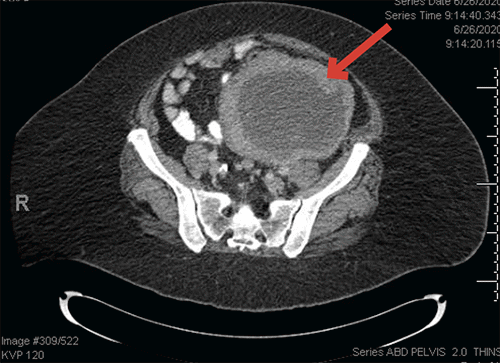

A 66-year-old woman with a history of diabetes mellitus, class II obesity, hypothyroidism, hypertension, and hysterectomy with bilateral salpingo-oophorectomy (BSO) for uterine leiomyoma that was performed 16 years prior presented to her primary care provider eight months after noticing a palpable lump inferior to her umbilicus. She reported increasing levels of pain in her left lower quadrant, fatigue, abdominal distension, and a decreased appetite, resulting in a 30-pound weight loss over four months. A physical exam was pertinent for a nontender palpable mass in the left lower quadrant. Computed tomography (CT) scan revealed a large, centrally necrotic mass measuring 13.4 × 11.0 × 14.0 cm in the left lower quadrant abutting the proximal sigmoid colon with noted enlargement of the left paraaortic, high rectal, perisigmoid, and left external iliac lymph nodes (Figure 1A). A CT-guided biopsy of the mass was concerning for a low-grade epithelioid neoplasm with immunohistochemistry positive for cytokeratin OSCAR, cytokeratin AE1/AE3, S100, smooth muscle actin (SMA), and weakly positive for epithelial matrix antigen (EMA) and calponin, which made it difficult to classify the tumor definitively. There was no evidence of metastatic disease on cross-sectional imaging of the chest or abdomen, and laboratory tests were within normal limits. A colonoscopy was performed due to the proximity of the tumor to the sigmoid colon. It showed congested mucosa within the sigmoid colon but no erosion of the tumor into the lumen.

Figure 1. Abdominal and Pelvic CT. Published with Permission

A) Note large, centrally necrotic mass in the left lower quadrant (red arrow)